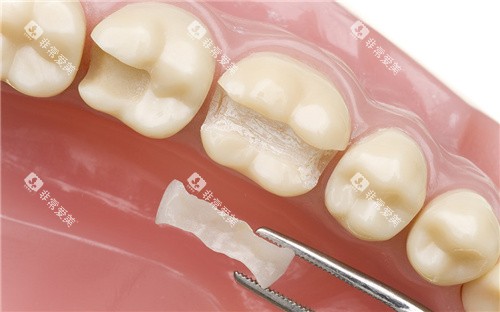

牙齿贴面可以改善牙齿的颜色、形状和大小,让牙齿更加美观。

郴州第三人民医院口腔科常见的牙齿贴面有瓷贴面和树脂贴面。

树脂贴面价格较为便宜,每颗牙齿的收费在300 - 800元左右。

但它的耐磨性和美观度相对瓷贴面较差。

瓷贴面的结果更好,更加美观、耐用,每颗牙齿的收费在1500 - 3000元左右。